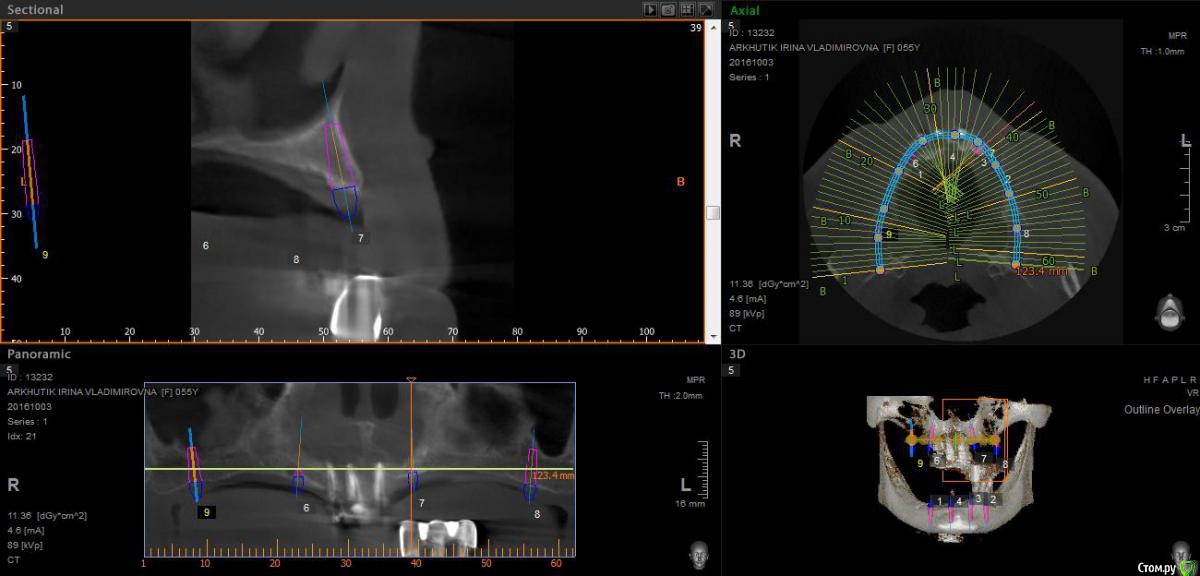

Rusty Опубликовано 5 октября, 2016 Поделиться Опубликовано 5 октября, 2016 Добрый день. К ортопеду обратилась пациентка 55-60 лет с такой ситуацией. Пришла с дочкой, дочь с мамой настаивали на несьемной конструкции, ортопед отправил на кт и вот. Не хочу планировать ей много хирургии, оцените и мой план пожалуйста и буду рад услышать советы по реабилитации пациента. По сути да) просто искал место куда есть возможность поставить, ортопед говорит тогда балка либо локаторы Ссылка на комментарий

Rusty Опубликовано 5 октября, 2016 Автор Поделиться Опубликовано 5 октября, 2016 На н/ч балка? Какие измерения в дист отделах? На в/ч мало четырёх. По три бы.На н/ч балка, в дистальных отделах над каналом около 3мм. На вч условий для установки больше 4 не нашел) Ссылка на комментарий

Nazim_NV86 Опубликовано 6 октября, 2016 Поделиться Опубликовано 6 октября, 2016 А на низ кроме блоков больше рабочих методов не вижу. Ссылка на комментарий